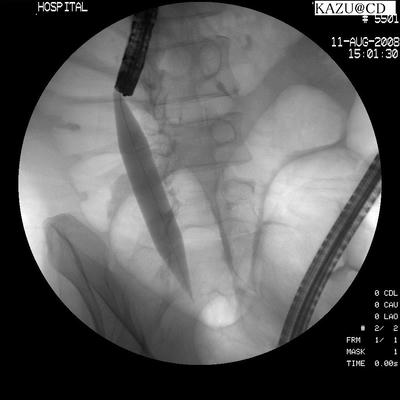

今回も画像を頂いてきたがスキャンの調子が悪いので前回の画像を載せときます

(2008年8月の画像)

白い半透明な物がバルーンです

レントゲンの画像も前回の分です

バルーンを膨らまします

レントゲン画像 狭窄部にバルーンを通したところ